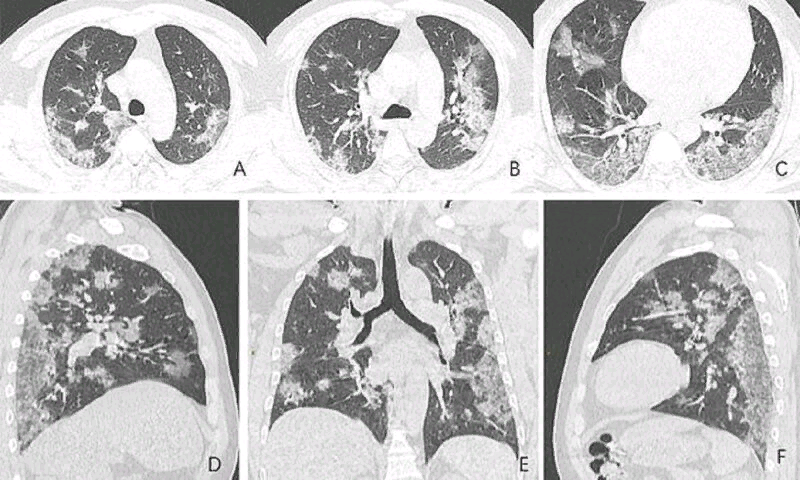

Шокирующие рентгеновские снимки 44-летнего пациента из Китая, умершего от коронавируса, показывают, что эта болезнь делает с человеческими легкими. Перед нами самое опасное осложнение вируса, переходящего в тяжелую пневмонию. Опубликованы рентгеновские снимки и компьютерная томография 44-летнего китайского пациента. По ним хорошо видно, как именно вирус разрушает легочную ткань. По утверждениям медиков, повреждения похожи на те, что обнаруживались в легких жертв атипичной пневмонии и ближневосточного респираторного синдрома. Рентгеновские снимки и томограммы легких 44-летнего пациента, умершего от коронавируса, были представлены китайскими врачами. Они дают подробную картину того, как вирус разрушает легкие человека. На снимках видны белые пятна в нижних отделах легких. Медики называют их «субплевральными уплотнениями по типу матового стекла». В этих областях воздушные пузырьки легких частично заполнены содержимым. Похожие поражения наблюдались также у пациентов с атипичной пневмоние